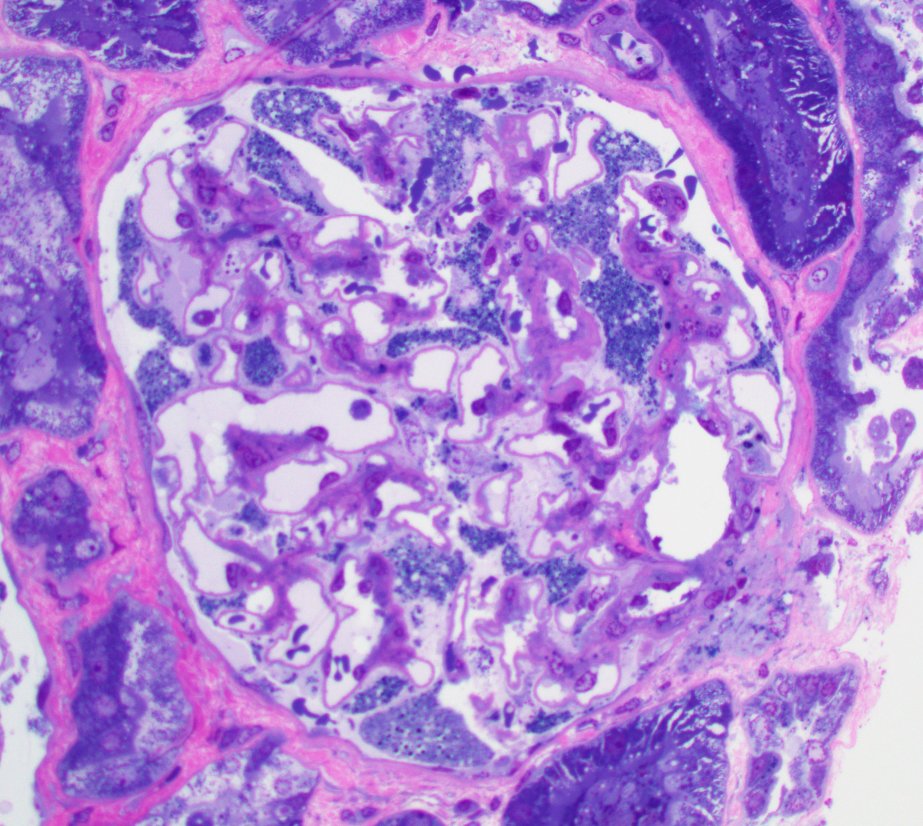

Mini case-series of crystal-storing histiocytosis (CSH) affecting predominantly glomerular loops with detailed literature review of renal CSH, images of one of the cases are depicted below, authors.elsevier.com/c/1Zh4S3uV~y8B…